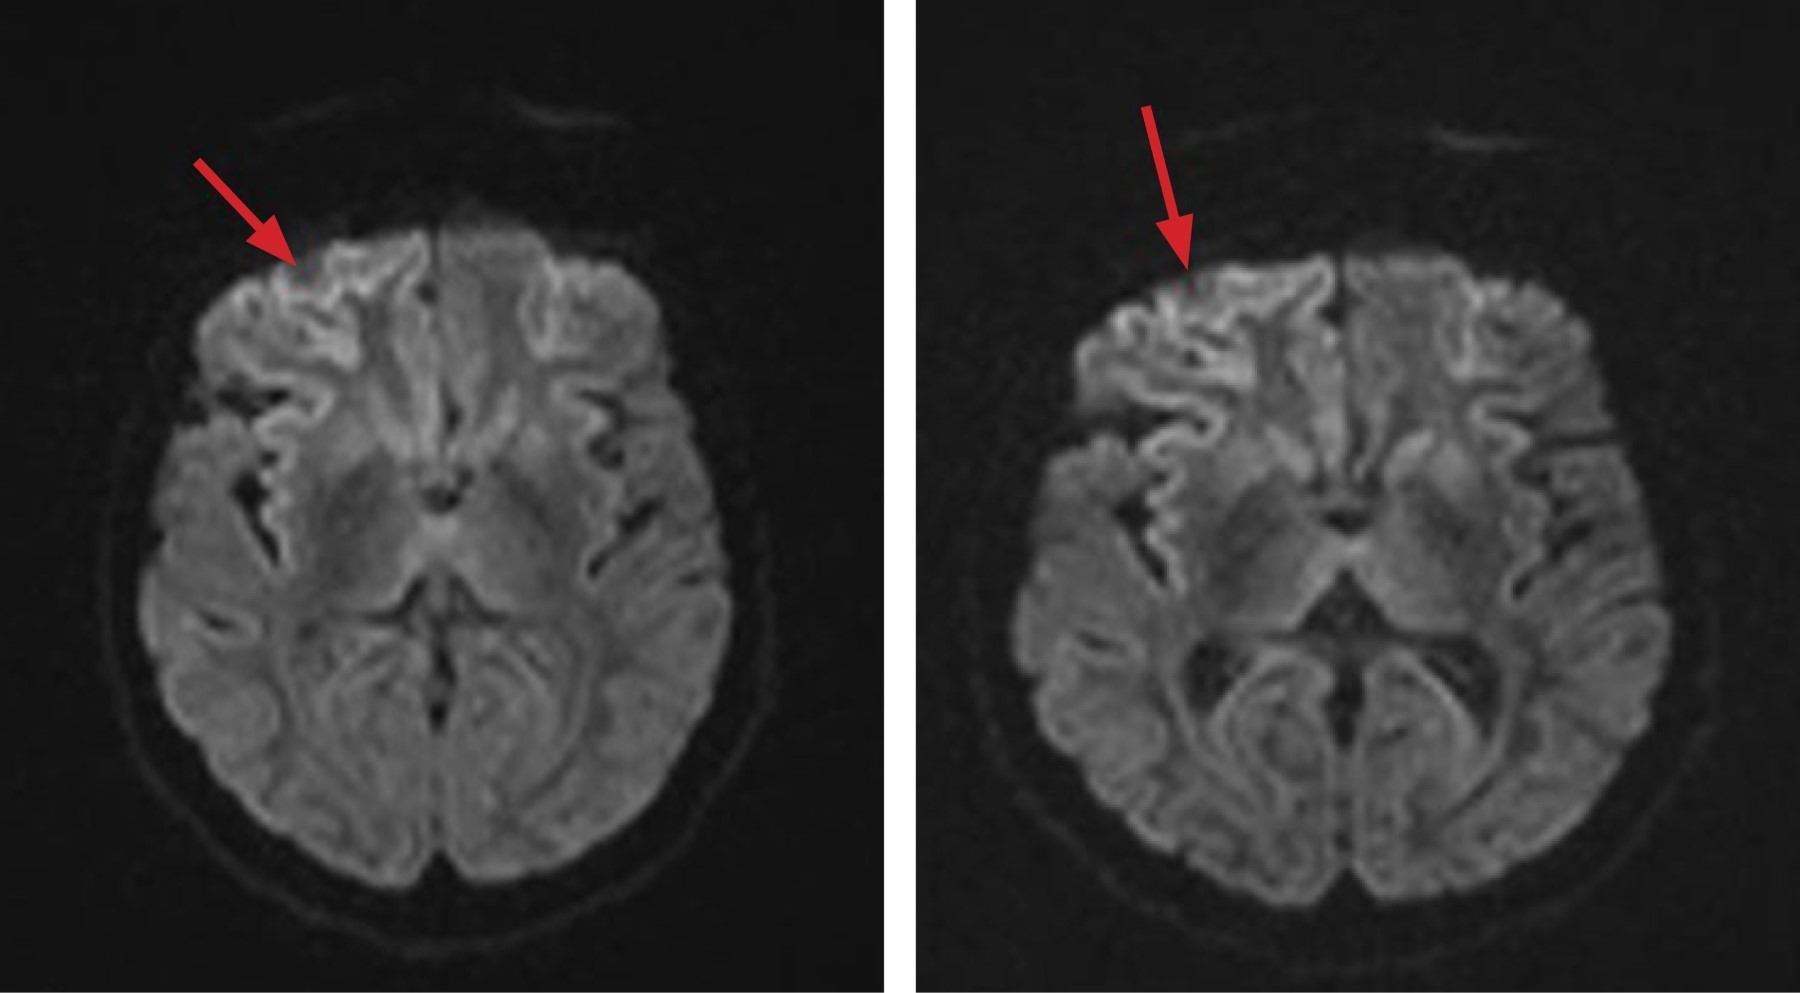

Hyperkinetic syndrome associated with rapidly progressive dementia. Report of a case of Creutzfeldt-Jakob disease in the General Hospital of Mexico

Creutzfeldt-Jakob disease (CJD) is a rare neurodegenerative condition with a fatal course; in Mexico its incidence is unknown; establishing the diagnosis is a challenge for the physician in our environment. And it should be suspected in the presence of rapidly progressing dementia associated with myoclonus, cerebellar involvement, visual and psychiatric disorders. The objective of this article is to present the case of a 59-year-old patient who presented with choreiform-type movement disorder and rapidly progressive cognitive impairment.

Figure 1

Figure 2